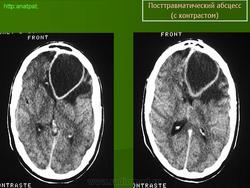

Абсцесс головного мозга – это очаговое скопление гноя в мозговом веществе, окруженное капсулой.

Возникают посттраматические абсцессы при проникающих ранениях, а также при закрытой травме. В последнем случае инфицирование происходит через кровь из отдаленного очага инфекции. Основными возбудителями являются стафилококки, стрептококки, реже грамотрицательная флора, нередко наблюдается сочетание нескольких возбудителей.

Компьютерная (КТ) или магнитно-резонансная (МРТ) томография головного мозга являются ведущими методами диагностики посттравматических абсцессов, позволяющих судить об их расположении, объеме, структуре, консистенции, содержимом, воздействии на вещество головного мозга. Для исключения опухолей головного мозга, туберкулом, паразитарных заболеваний проводится ОФЭКТ (однофотонная эмиссионная компьютерная томография).